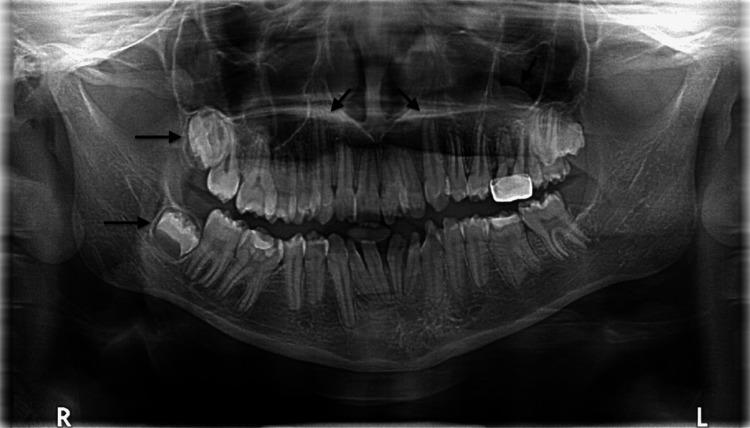

Focal dermal hypoplasia (FDH), also known as Goltz syndrome, is a rare syndrome described in the literature. Patchy skin hypoplasia is the most evident sign. Hyperpigmentation, hypopigmentation, papillomas, limb defects, and orofacial manifestations have also been reported. A 12-year-old Saudi girl with unremarkable family history presented with FDH. The diagnosis was confirmed using a genetic study. Physical examination revealed asymmetrical streaks of vermiculate dermal atrophy, telangiectasia with hyperpigmentation, and hypopigmentation on the left half of the face, trunk, and bilateral extremities. It appears along Blashko lines. No mental impairment was observed. Intraoral examination generalized plaque-induced gingivitis with erythematous gingival hyperplasia. Examination of the teeth showed generalized enamel hypoplasia with abnormal tooth formations, malalignment, microdontia, spacing and tilting, and minimal caries. As reported cases of FDH are rare worldwide, this syndrome is yet to be fully understood. As the manifestation of the syndrome varies among cases, the management of each case is unique. This emphasizes the importance of reporting cases of FDH.

局灶性真皮发育不全(FDH),也称为戈尔茨综合征,是文献中描述的一种罕见综合征。片状皮肤发育不全是最明显的体征。也有报道称存在色素沉着过度、色素减退、乳头状瘤、肢体缺陷和口面部表现。一名12岁的沙特女孩,家族史无异常,患有局灶性真皮发育不全。通过基因研究确诊。体格检查发现左侧面部、躯干和双侧肢体有不对称的蠕虫状皮肤萎缩条纹、伴有色素沉着过度的毛细血管扩张和色素减退,沿布拉斯科线分布。未观察到智力障碍。口腔检查发现广泛性菌斑性牙龈炎伴牙龈红斑增生。牙齿检查显示广泛性釉质发育不全,伴有牙齿形态异常、排列不齐、过小牙、牙间隙和牙倾斜,以及轻度龋齿。由于全球范围内报道的局灶性真皮发育不全病例很少,该综合征尚未被完全了解。由于该综合征在不同病例中的表现各异,每个病例的治疗都是独特的。这强调了报告局灶性真皮发育不全病例的重要性。